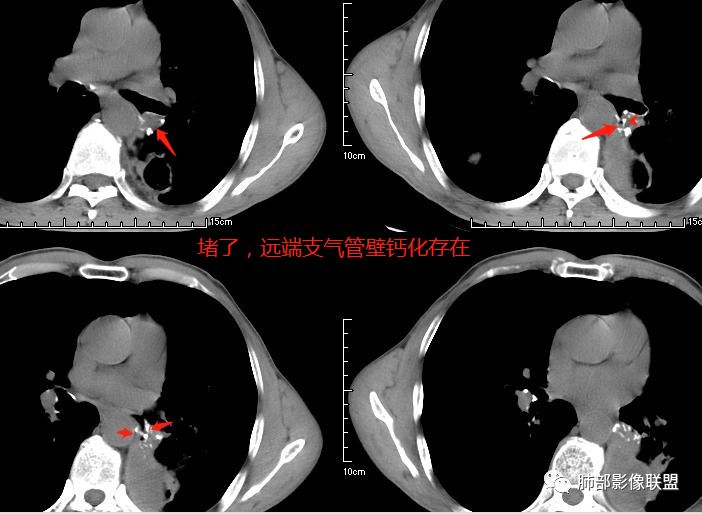

患者老年男性,咳嗽、咳痰、痰中带血伴胸闷2月余。长期大量吸烟史。查肝肾功能、血糖、血脂、心肌酶、电解质、血沉、C反应蛋白、抗“O”、类风湿因子、抗核抗体谱无明显异常。肿瘤标志物提示NSE、CYFRA21-1稍升高。胸部CT:肺气肿背景,左肺下叶后基底段不规则肿块影,见支气管截断,内见大片状低密度区及部分血管影,增强轻度强化,远端空洞形成。双肺多发不规则实性结节影、见毛刺、胸膜牵拉及血管集束,结节内见空洞形成,部分可见血管影,多位于胸膜下。双肺见多发肺大泡。综合考虑左下肺恶性病变并双肺转移。鳞癌或淋巴瘤可能。鉴别血管炎性病变及真菌感染。

张延军:双肺多发结节,空洞影,后者洞壁厚薄不均匀,部分腔内丝丝落落,呈分叶征,边缘见毛刺影,病灶大部分位于胸膜下,与血管相连,右肺下叶前基底段结节近段支气管截断,远端见空腔。左肺下叶病灶密度不均,背段支气管壁增厚,管腔狭窄。考虑1.双肺下叶占位性病变伴肺内空洞性转移 2.多原发的占位 3.肉芽肿性血管炎代排。

空洞型肺转移瘤成因尚不完全明确, 可能与鳞癌中心角化物排空 、腺癌黏液样退变后黏液排空 、肿瘤血供不足引起坏死 、肿瘤继发脓肿 、化疗等机制有关,其中部分薄壁囊腔样结可能是肿瘤细胞沿着原有的肺大泡或其它囊性结构生长或者肿瘤向小支气管侵犯引起活瓣性阻塞而形成 ,但无一种机制能解释全部现象。空洞或囊腔大小并不反映病情变化, 其临床意义不大, 而瘤灶的数目及大小, 特别是瘤灶实性成分的多少才可能更准确反映病情变化。肺癌形成空洞与其肿瘤本身性质有明显联系,肿瘤分化程度差,倍增时间越短,恶性程度越高,组织液化坏死形成空洞倾向越明显;鳞癌空洞偏大,内缘不规则,常易形成X线平片中癌梁样改变与CT中壁结节样改变;而腺癌空洞大小不定,洞内分隔明显,内缘不规则,且较难于形成壁结节等改变;合伴空洞的肿瘤边缘情况也对判断肿瘤性质有帮助。

其中囊样空洞和小环形空洞属于薄壁空洞,泡样空洞和不规则空洞属于厚壁空洞,其中腺癌空洞型肺转移瘤主要表现为小环形空洞,以下3个病例均表现为小环形空洞的转移瘤:

本病例左肺下叶肿块,有深分叶、毛刺、胸膜牵拉凹陷、支气管截断及纵隔内淋巴结肿大等征象,都均支持病灶为恶性,如腺癌,而且叶间裂的多发结节也提示是腺癌来源可能大;双肺多发结节、肿块,大部分病灶有分叶、毛刺及胸膜凹陷的恶性征象,与原发肿瘤本身的性质有关,所以应该与左肺下叶肿块同源,而且双肺多发病灶内空洞也具有多样性;

此病例中空洞形态多样,内壁不光整,有分隔影,周围未见明显卫星灶及钙化灶,结核不太符合;患者病史慢性病史,无明显发热,缺乏中毒临床表现,急性感染基本排除;各种中性粒细胞胞浆抗体阴性,没有鼻窦炎,肾脏等病史,基本排除血管炎;霉菌性空洞常见于免疫机能低下者, 常为空洞、肺炎、伴“ 晕圈”征的结节及支气管扩张合并存在。